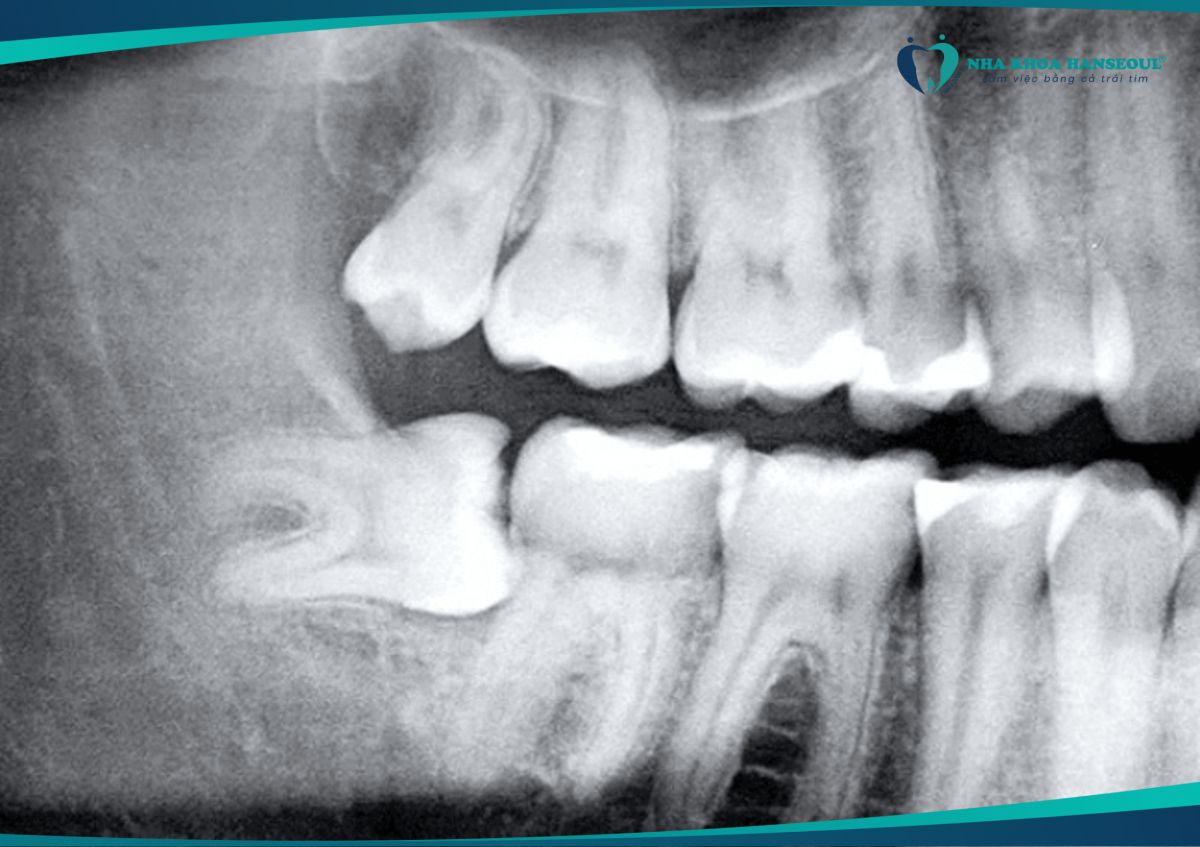

Những biến chứng thường gặp sau khi nhổ răng số 8 và cách xử lý

04/07/2025